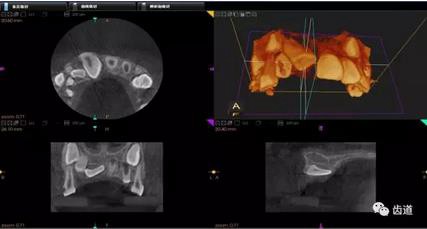

2、下頜磨牙阻生

下頜第二第三磨牙阻生口腔曲面斷層片影像

下頜第二第三磨牙阻生CBCT影像定位

三種圖片的影像學(xué)比較